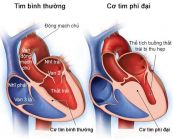

Bệnh cơ tim phì đại là tình trạng tâm thất trái hoặc toàn bộ cơ tim, thất phải, mỏm tim bị phì đại khiến dày lên bất thường. Cơ tim phì đại là bệnh di truyền với tỷ lệ mắc bệnh là 1/500. Để hiểu rõ hơn về hội chứng này trên điện tâm đồ như thế nào, mời các bạn cùng tham khảo bài viết dưới đây nhé!

Bệnh cơ tim phì đại (BCTPĐ) là bệnh lý ảnh hưởng đến cơ tim, trong đó phần cơ tim trong thành tim ở tâm thất dày lên. Vậy trên điện tâm đồ, bệnh cơ tim phì đại được thể hiện như thế nào? Mời các bạn tham khảo bài viết sau đây nhé!